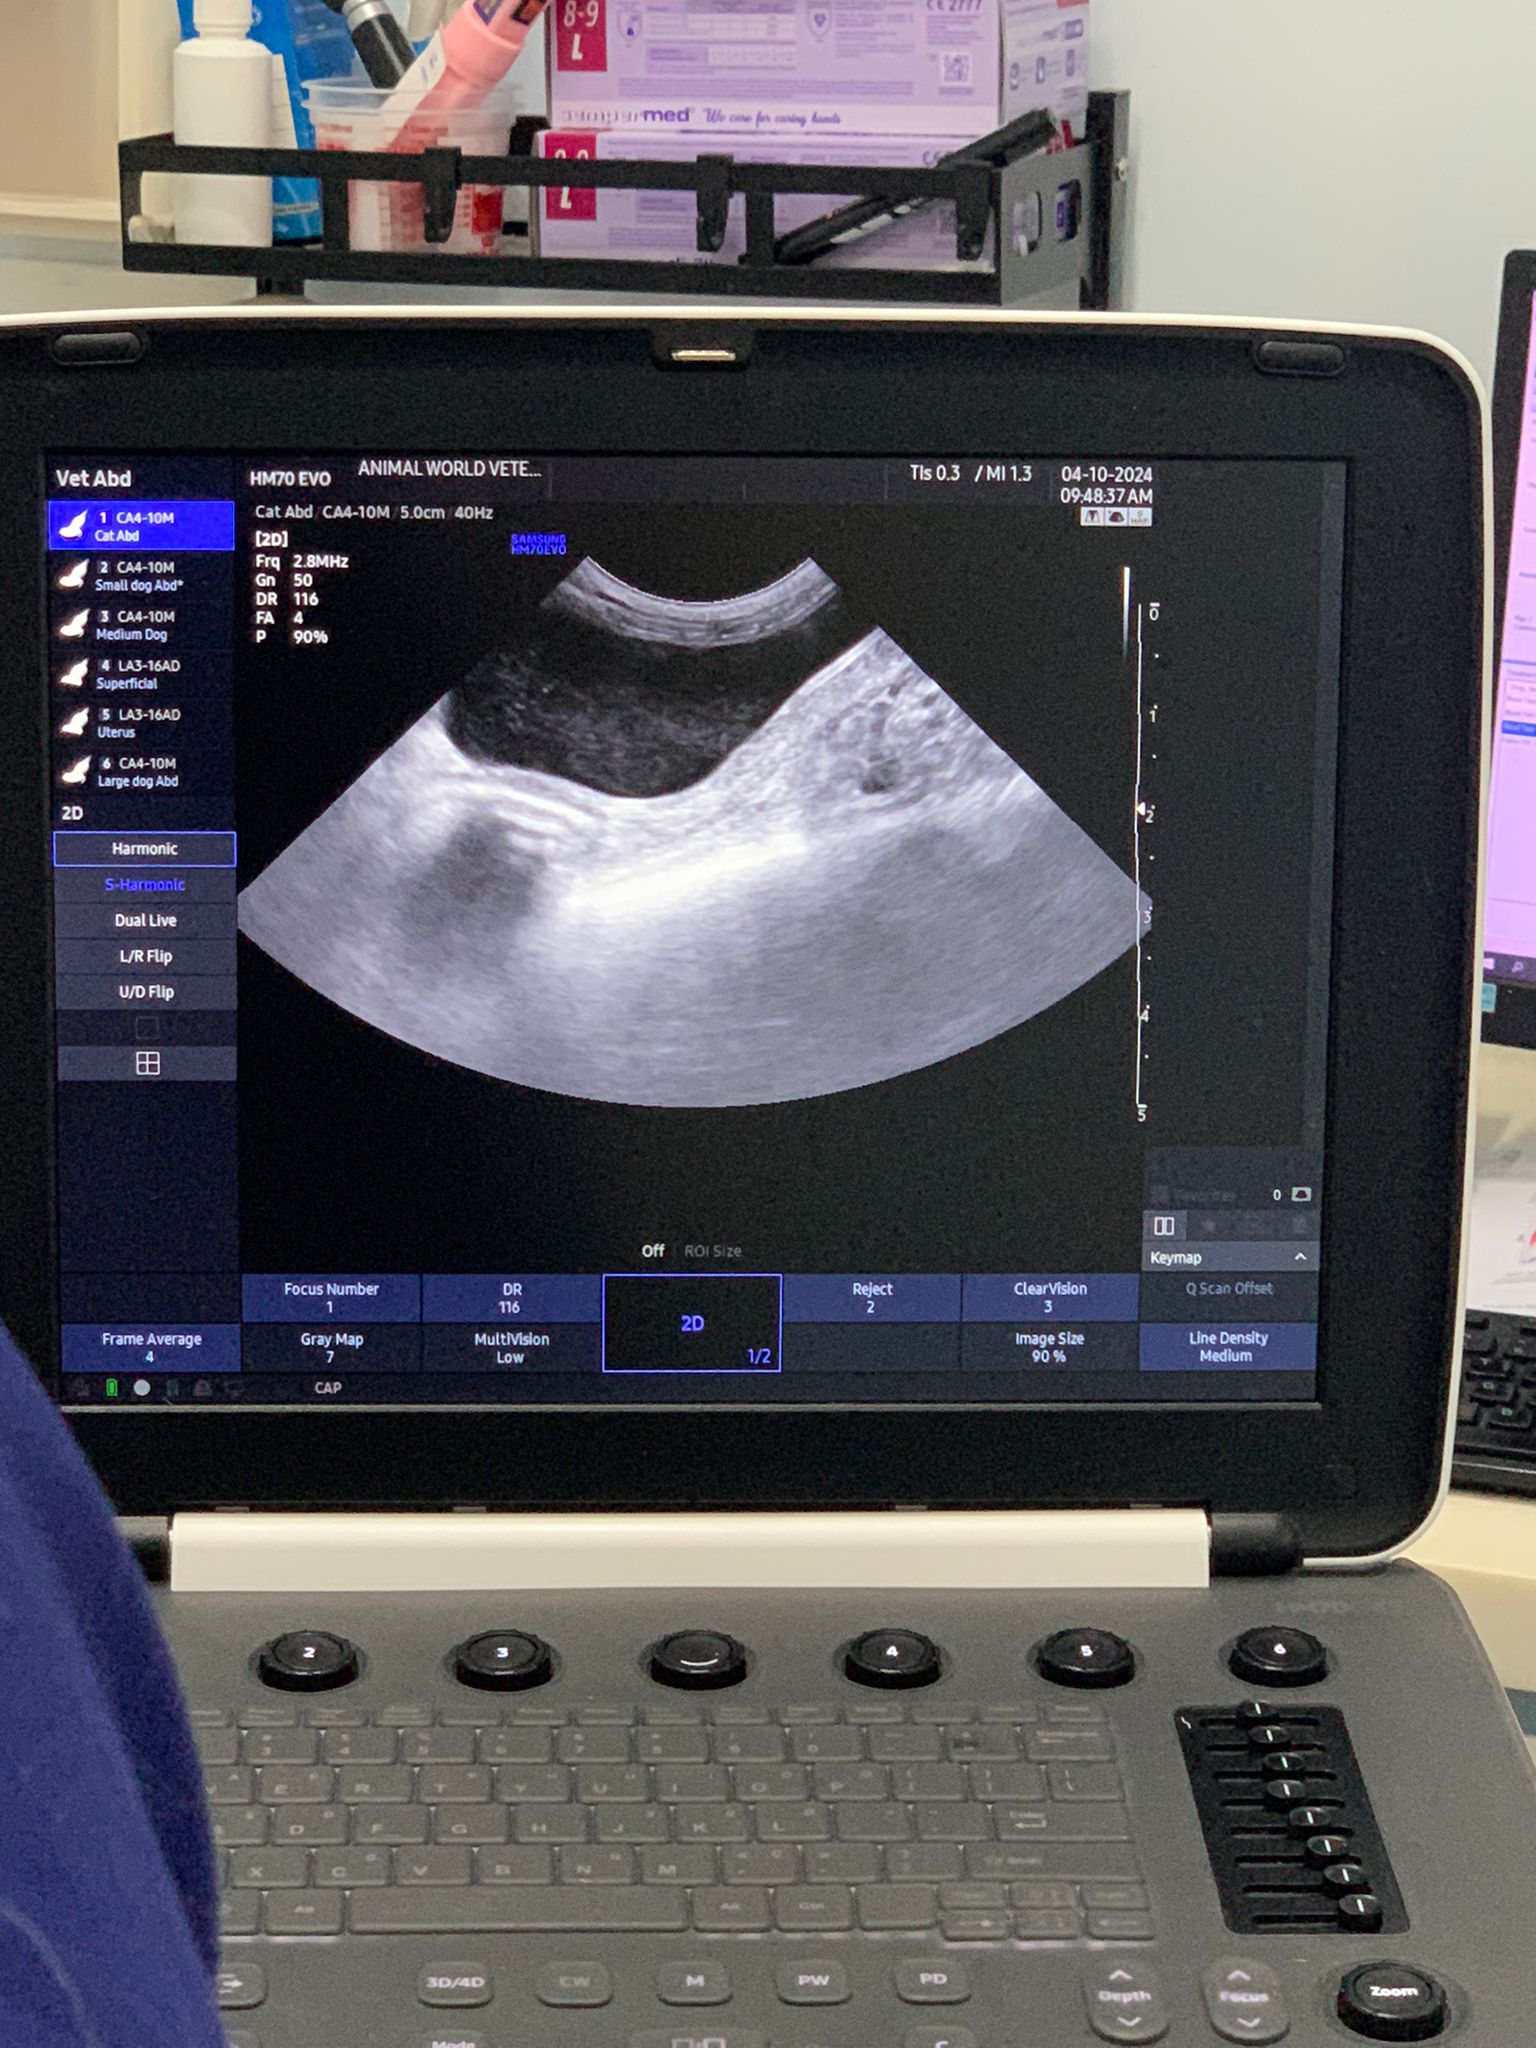

10.30am: seen dr Brandon.

3.02kg – about the same weight didn’t gain weight ah. Eat so much food didn’t gain weight ah

Told vet she eat a lot poo a lot

He said she got some sound fr the nose, but I didn’t notice any sigh of flu, so that can be an early sign of flu.

Cherie quite Zai, draw blood from jacular, Alex hold her, no issue at all. Pro.

Taken Cbc Chem10 lytes.

Dr shave her to check for old scar. Erm but he can’t find it. He didn’t say anything, not sure he willing to issue a PE cert for her or not

She don’t like pple touch her belly itchy.

10.36am: m/c done

10.37am: nails cut fr the hind legs no ingrowth there, but very long

Front cut, and also clean off the blood. Lucky the ingrowth not like mama bai bai type. She is super Guai and calm. Pre empt her for the past days are useful. And Alex is a calm handler also.

Dr use u/s to draw urine, 3ml. Will do urine analysis only, if got any issue then add on microscopy

11.05am: he not issuing cert for Cherie. so papa got to try to find her old cert or the vet that Cherie is spayed

1107am: results out. Cherie is stage 1/2 kidney problem cos though crea is only 2.1, her urine is not concentrated sg 1.019 (can see is alr diluted) but not the type that need Subcut yet if her kidneys / her drinking habit can still compensate. I did notice she keep drinking water which is good.

HCT 38.3%. Potassium slight low 3.4

11.14am: fiv felv results out: both negative

Back from vet and she is still active walk about